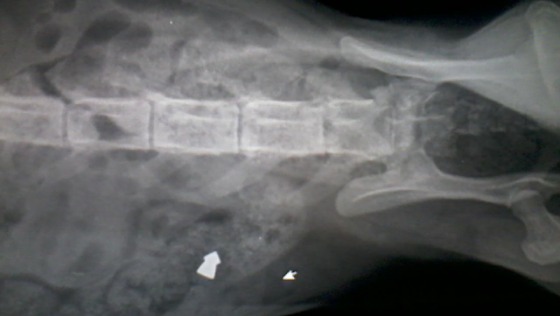

RTG wykazało śrut wewnątrz chudego i kruchego ciałka :(.

APELUJEMY DO MIESZKAŃCÓW PUDŁOWCA - TO JEST NASTĘPNY KOT POSTRZELONY ŚRUTEM!

POPRZEDNIEJ POSTRZELONEJ kotce TRZEBA BYŁO AMPUTOWAĆ ŁAPKĘ. Nie wiemy jaki los czeka RUDZIKA :(